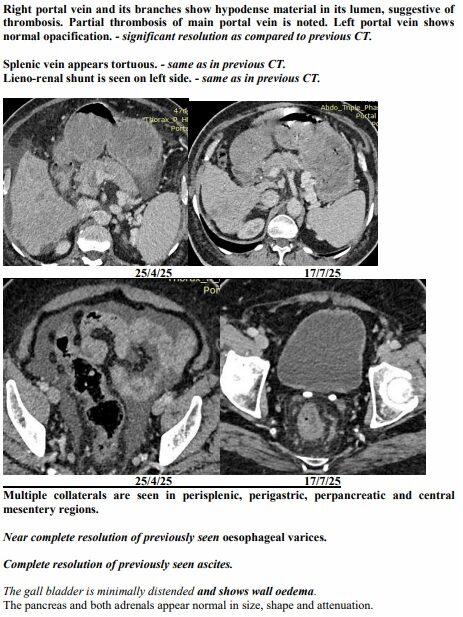

Surat (Gujarat) [India], August 22: On a hot April afternoon in Surat, the Patel family sat in a crowded hospital waiting room, clutching a CT scan report that felt heavier than paper. The words were sharp, merciless: advanced liver cancer, spread across both lobes, blocked veins, fluid buildup, bone changes. For 74-year-old Ravjibhai (name changed), the doctors spoke plainly: there was no cure left, only comfort care.

Yet just three months later, on another afternoon in July, the same family stared at a different scan. The tumours had shrunk to one patch. Blood was flowing again. The swelling was gone. Even the alarming tumour marker that had shot up to 1,000 ng/mL had fallen to 10, back in the safe zone. For a man who had been fading fast, it was a turnaround no one in the room dared to predict.

The July scan sealed what they were already feeling at home. The many shadows in his liver had shrunk into one. His abdomen, once swollen with fluid, was flat again. His numbers, which had scared even seasoned oncologists, were suddenly within range.

A senior radiologist who reviewed both reports told this correspondent, “Such a reversal in advanced liver cancer is extremely rare. Clinically, it borders on the unbelievable.”